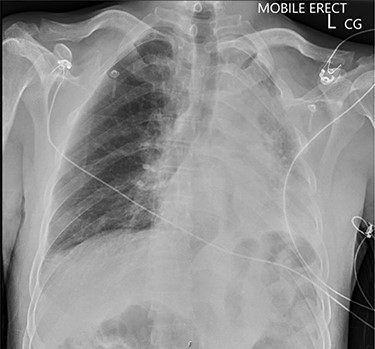

Chest X-ray illustrating complete collapse of the left lung lobe.

On presentation, chest X-ray illustrated a prominent proximal descending thoracic aorta contour and a completely collapsed left lung (Fig. 1). On computed tomography angiogram (CTA), the patient was found to have a large saccular aneurysm measuring 5.0 × 5.0 × 5.0 cm in size, arising from a focal location of the proximal descending thoracic aorta distal to the origin of the left subclavian artery with evidence of contained rupture (Fig. 2). The mass was found to be causing significant external compression of the left main bronchus leading to significant effacement of the left main primary bronchi leading to extensive collapse in both left upper and lower lobes and overall reduction in volume of the left hemithorax (Fig. 3).